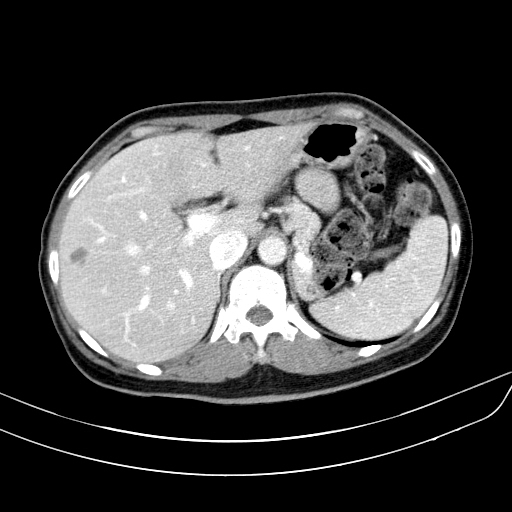

왼쪽 영상이 arterial phase, 오른쪽 위는 portal phase, 마지막으로 오른쪽 아래 영상이 delayed phase 영상입니다. arterial phase에서도 어느정도 조영증강이 되어 주변의 간실질과 비슷한 감쇄도를 보이고 있습니다. 다만, portal 및 delayed phase에서 조영제가 완전히 빠져나가 뚜렷한 저음영으로 보이는 wash-out 양상을 보이지 않고 조영제가 병변 안에 어느정도 머물러 있습니다.

이러한 양상으로 볼 때 간세포암보다는 이형성 결절(dysplastic nodule)일 가능성이 커 보이므로 초음파영상을 통한 추적관찰을 하게 된 케이스입니다.